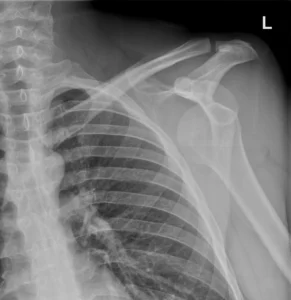

Luxación glenohumeral anterior

Radiografia de hombro izquierdo, proyecciones AP. La cabeza humeral está descentrada respecto a la glenoides, con desplazamiento anteroinferior (la forma exacta puede variar según proyección). Esto es el dato esencial: no hay congruencia glenohumeral.